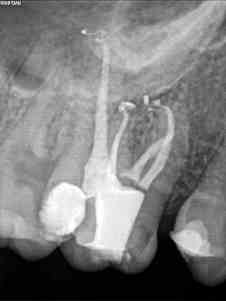

Todos los casos los tratamos igual, con ayuda del microscopio, localizamos los cuatro conductos, instrumentamos con sistema Mtwo, y obturamos con sistema de condensación vertical con ola contínua para hacer el downpack y pistola Obtura II para hacer el backfilling.

Lo que tienen estos tres casos en común, y por lo que decido colocarlos, es por la importancia que tiene la irrigación, por que hay veces que aunque en molares superiores localicemos el conducto Mesio-palatino,  puede que su salida se bifurque y nuestra lima no pueda seguir el conducto por que tiende a seguir recto uniendose al MV.